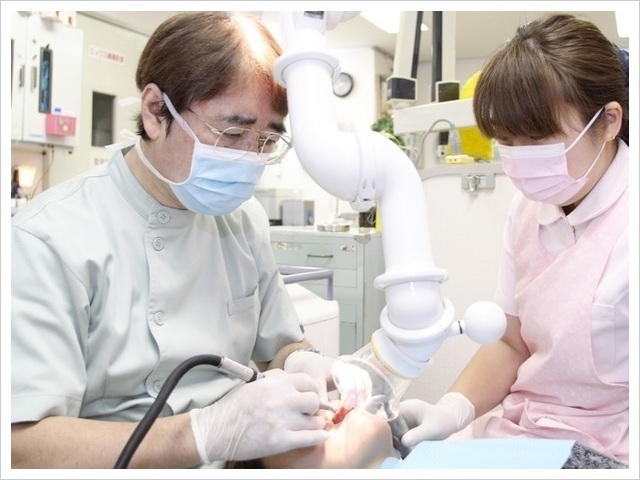

友田歯科では、歯を削ったり、神経を採ったり、歯を抜くような治療は、極力ないように努力しています。また、皆さんが一番嫌な注射も、特殊な器具を使って、痛みをほとんど感じないようにしています。

麻酔を工夫することで、

ほとんど痛みのない治療を実現。

痛みに配慮した治療を行っています

痛みが怖くて歯医者さんに行けない・・・そんな方を一人でも多く助けたいと考え、当院では痛みをほとんど感じない治療を行っています。